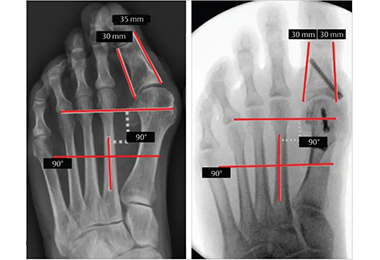

• Hallux Valgus Correction Guiding Tools

Hallux valgus, commonly known as bunions, is a prevalent foot deformity where the big toe deviates towards the other toes, often causing pain, discomfort, and difficulty in walking. For those suffering from severe cases, surgical correction becomes a viable option. In recent years, the advent of hal Read More

• Minimally invasive hallux valgus surgery

Hallux valgus is a bony deformity at the base of the big toe, characterized by a lateral deviation of the toe and a painful protrusion of the metatarsophalangeal (MTP) joint. While non surgical treatments like orthotics or footwear modifications may alleviate symptoms, surgery is often recommended f Read More